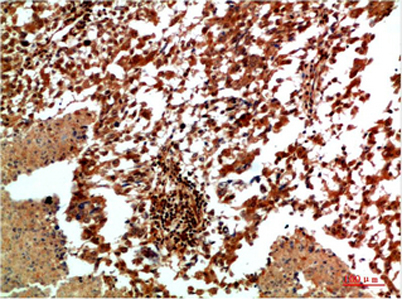

| Dilutions: | WB 1:500-2000,IHC-p 1:50-300 |

| Background: | The protein encoded by this gene is a member of the MAP kinase family. MAP kinases act as an integration point for multiple biochemical signals, and are involved in a wide variety of cellular processes such as proliferation, differentiation, transcription regulation and development. This kinase targets specific transcription factors, and thus mediates immediate-early gene expression in response to various cell stimuli. It is most closely related to MAPK8, both of which are involved in UV radiation induced apoptosis, thought to be related to the cytochrome c-mediated cell death pathway. This gene and MAPK8 are also known as c-Jun N-terminal kinases. This kinase blocks the ubiquitination of tumor suppressor p53, and thus it increases the stability of p53 in nonstressed cells. Studies of this gene's mouse counterpart suggest a key role in T-cell differentiation. Several alternative |